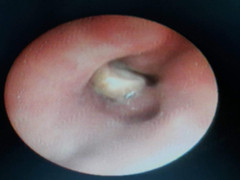

Con vắt rừng dài 8 cm sống 10 ngày trong mũi của bệnh nhân

Sau nhiều ngày chảy máu mũi rả rích, cảm giác đau, nhột trong mũi, thiếu niên 15 tuổi đi khám và được bác sĩ gắp ra con vắt dài 8 cm.